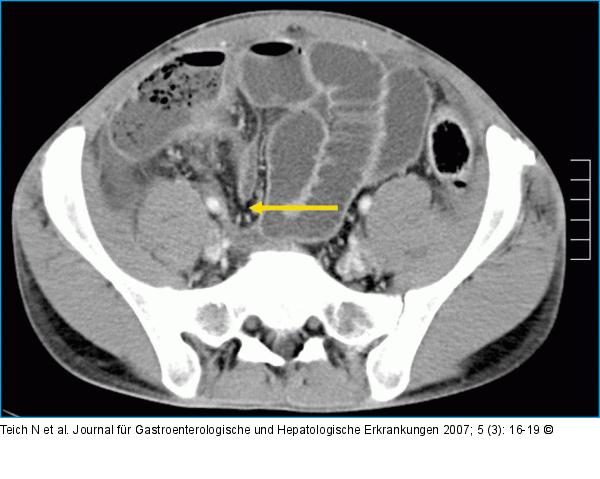

Abbildung 4: Ileum Computertomographische Darstellung eines längerstreckigen entzündlichen Verschlusses des terminalen Ileums (Pfeil) mit prästenotisch dilatiertem Dünndarm und einer geringgradigen Koprostase im Zökum. Nebenbefundlich finden sich erneut Residuen des klinisch remittierenden Mb. Bechterew. |

Abbildung 4: Ileum

Computertomographische Darstellung eines längerstreckigen entzündlichen Verschlusses des terminalen Ileums (Pfeil) mit prästenotisch dilatiertem Dünndarm und einer geringgradigen Koprostase im Zökum. Nebenbefundlich finden sich erneut Residuen des klinisch remittierenden Mb. Bechterew. |